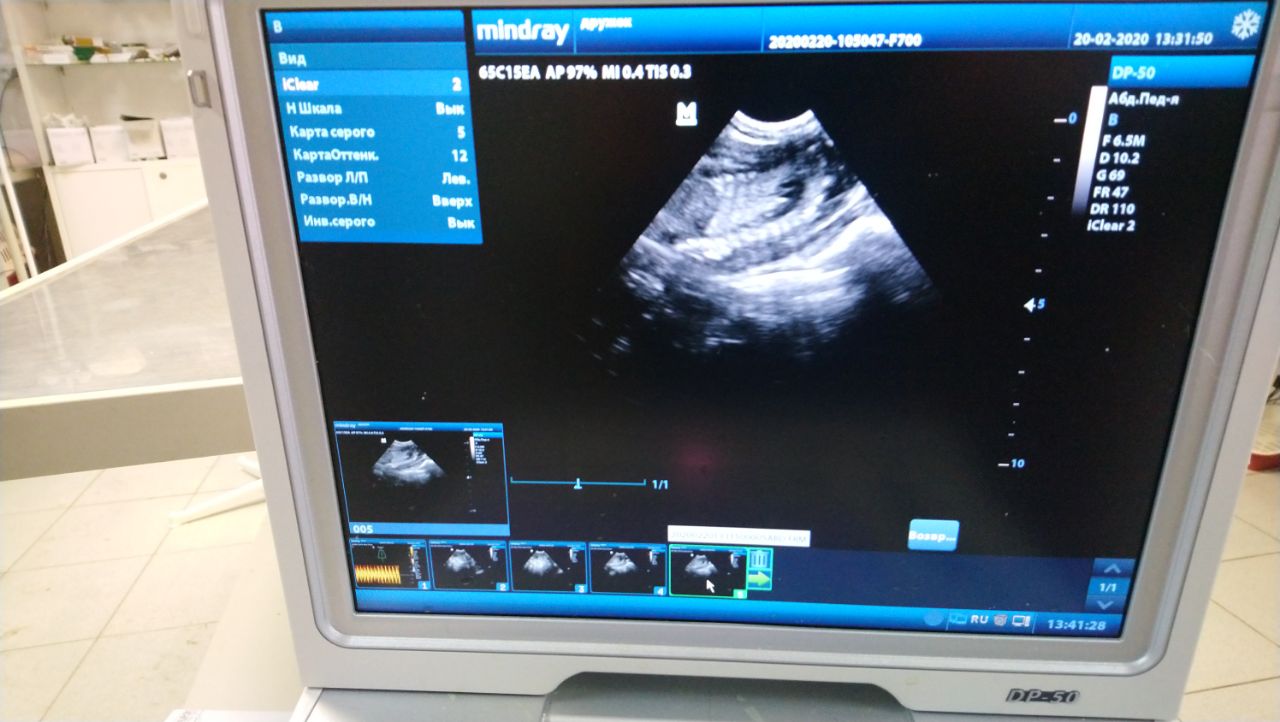

Ультразвуковое исследование (УЗИ)

Ультразвуковое исследование - современная процедура в ветеринарии мелких домашних животных, используемая для оценки изменений внутренних органов. При помощи УЗИ возможно оценить состояние органов брюшной полости, сердца, глаз, органов репродуктивной системы. УЗИ - метод, основанный на принципе эхолокации. Ультразвуковой передатчик излучает звуковые волны высокой частоты (2-15 мегагерц). Волны попадают на объект, отражаются от него (отражаемость зависит от плотности элементов тела) и поступают в принимающее устройство, интерпретирующее их в виде картинки на экране монитора. Чем выше частота ультразвуковой волны, тем меньше глубина проникновения в ткань и лучше разрешение близко расположенных объектов.

УЗИ плохо проходит через «воздушные» органы и кости, исследование которых затруднено. В каких случаях может быть рекомендовано УЗИ